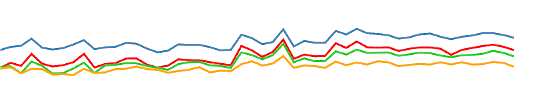

BH-induced CVR: Issues

Two problems:

- There's a measurement delay, and regional variations of the physiological delay

- The BH task presents collinear motion to signal of interest

Motion

CO2

BOLD

BH-induced CVR: Issues

Two problems:

- There's a measurement delay, and regional variations of the physiological delay

- The BH task presents collinear motion to signal of interest

Motion

CO2

BOLD